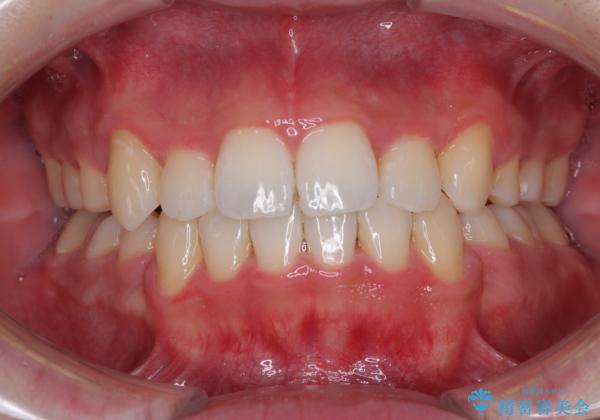

上下の八重歯とクロスバイト ワイヤー装置での抜歯矯正

- 八重歯とクロスバイトを気にして来院された患者様です。

上下ともに八重歯が顕著であり、前歯のクロスバイトがあったため、上下左右の第一小臼歯4本を抜歯し、ワイヤー装置での抜歯矯正を行うこととしました。

前歯の歯列が整ったことで、歯磨きが大変やりやすくなり、患者様には大変満足していただけました。